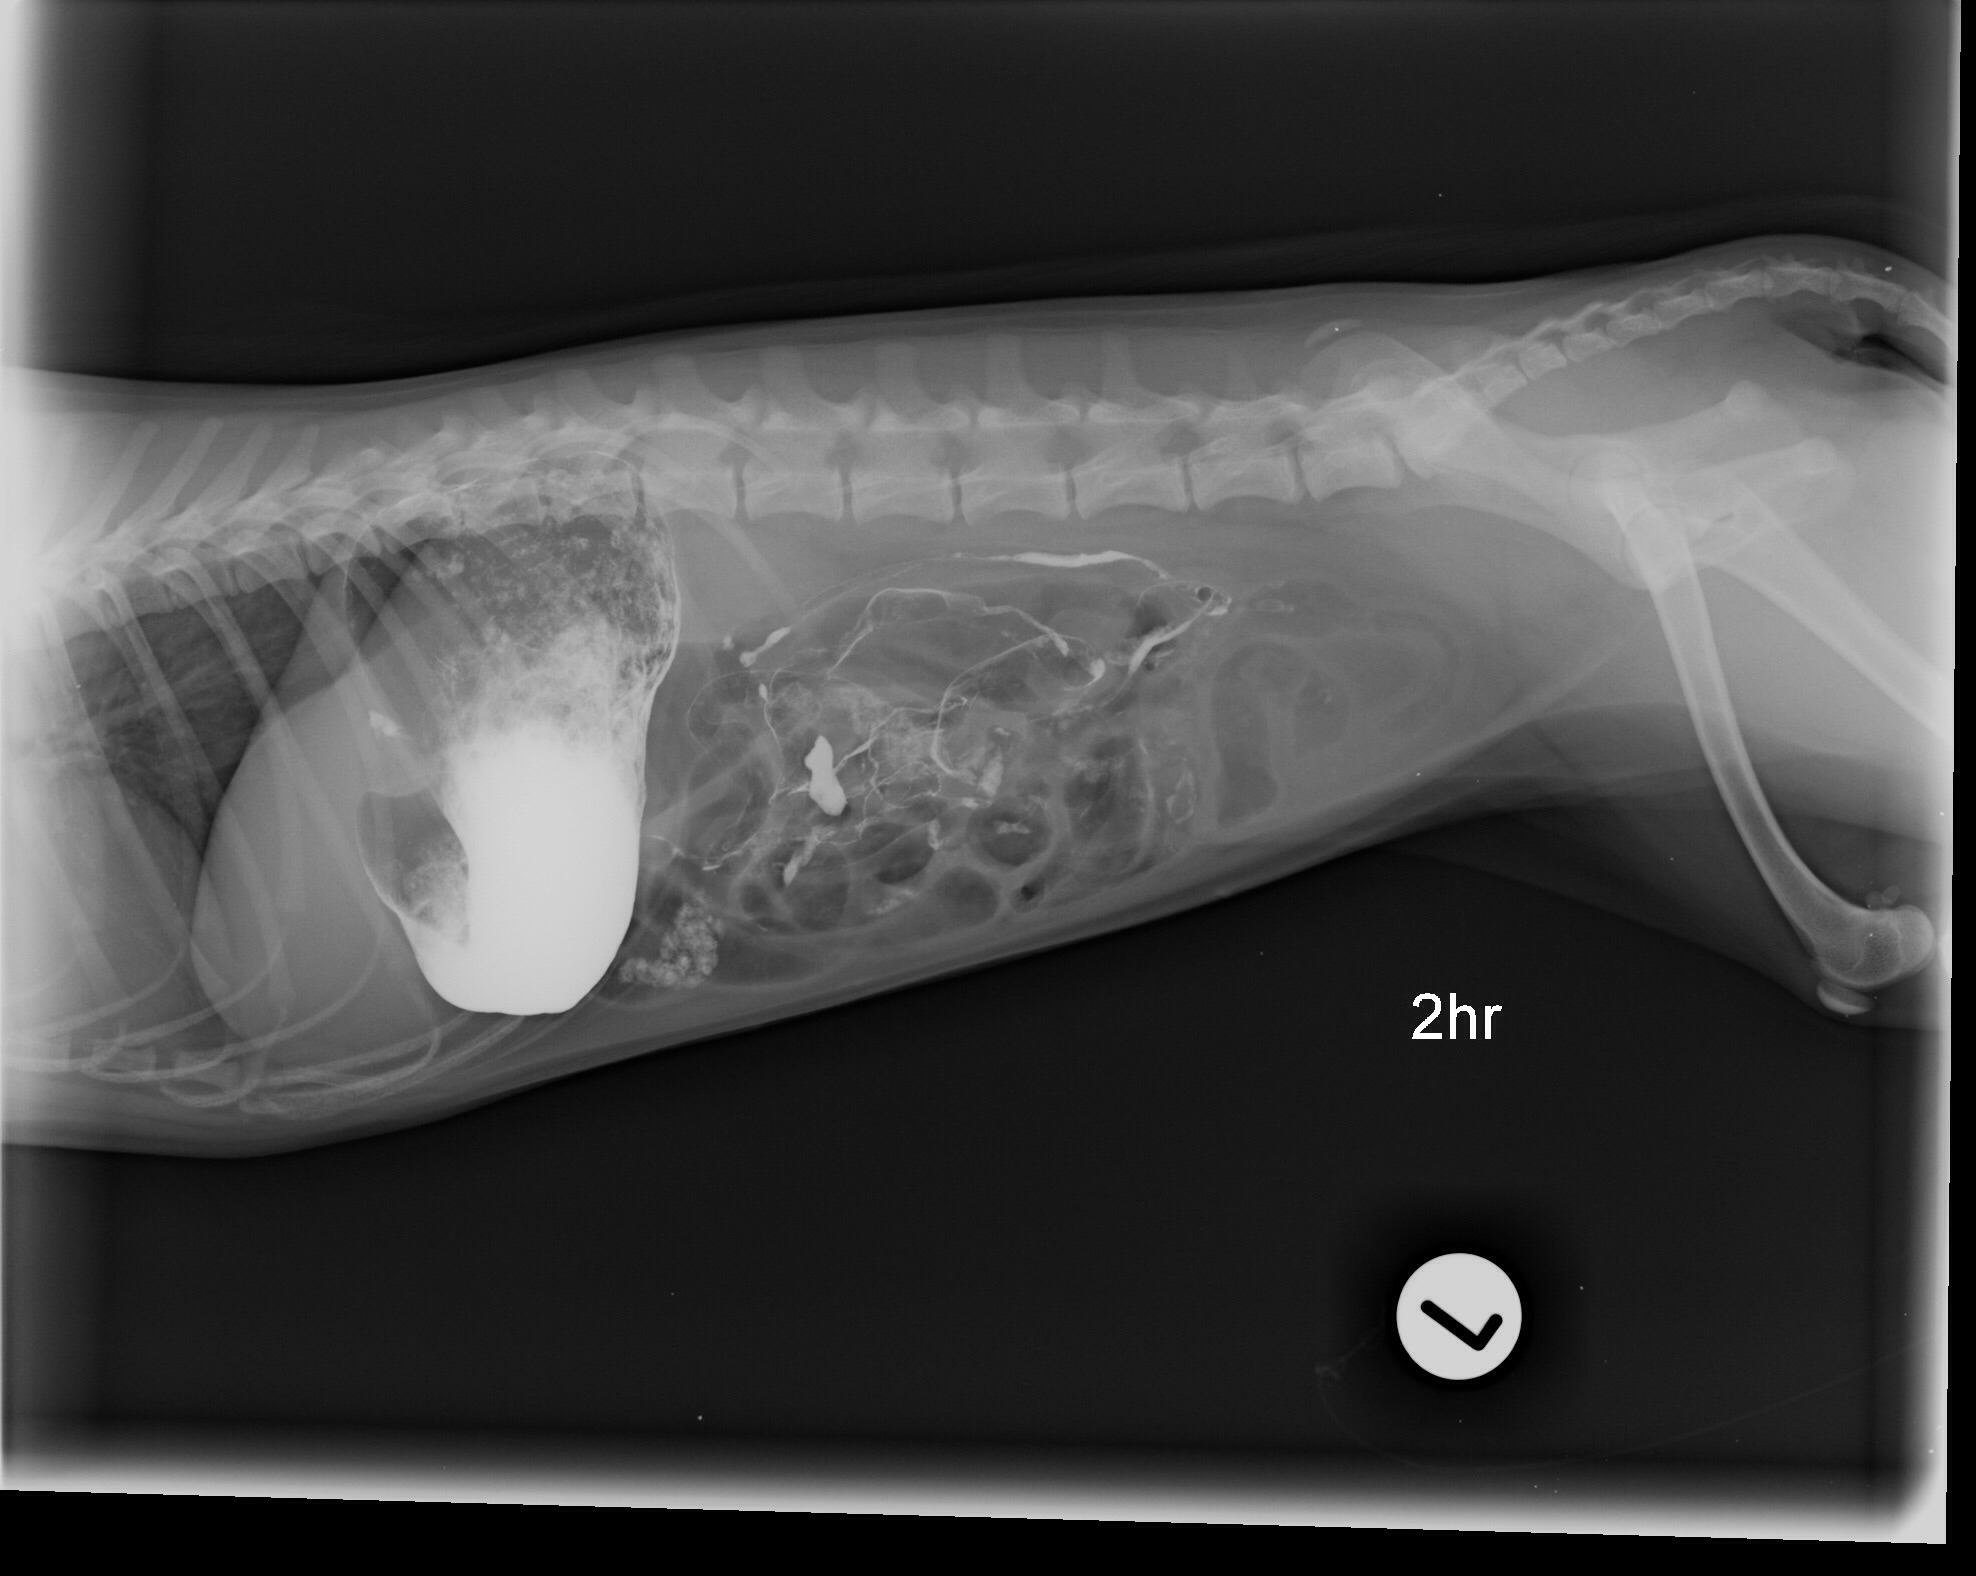

ديروز من بردمش دكتر و اونا نظرشون اين بود كه ممكنه چيزي قورت داده باشه و توي شكمش گير كرده باشه. سوفي xray شد و گفتند مقدار زيادي گاز توي شكمش هست، بهش berim contrast دادن و يكساعت بعد دوباره xray گرفتن و فقط مقدار كمي از كانترست خارج شده بود كه ميگفتن طبيعي نيست بايد خارج ميشده، صبح باز هم xray شد و بيشتر كانترست خارج شده بود ولي ميگفتن چون هنوز كمي اش مونده ممكنه چيزي باشه و بايد عمل بشه، اما من هنوز متقاعد نشدم، آيا واقعا اگه چيزي بود نبايد توي سه بار عكس گرفتن اونم بعد كانترست نباد نشون بده؟ سوفي بينهايت آب بدنش كم شده و واقعا نياز به سرم داره، ديگه بالا نياورده اما تا ديشب اسهال داشت. اونا بيست و چهار ساعت براي عكس نگهش داشتن تازه امروز گفتن بايد بيست و چهار ساعت ديگه بمونه براي سرم، اينجوري من فقط شارژ ميشم بدون اينكه مطمئن باشم قضيه چيه و اين كوچولوي زبون بسته هم هنوز حالش خوب نيست، من جواب ها رو براتون ايميل ميكنم، اگه نظرتون رو بگيد واقعا مديونتون ميشم.